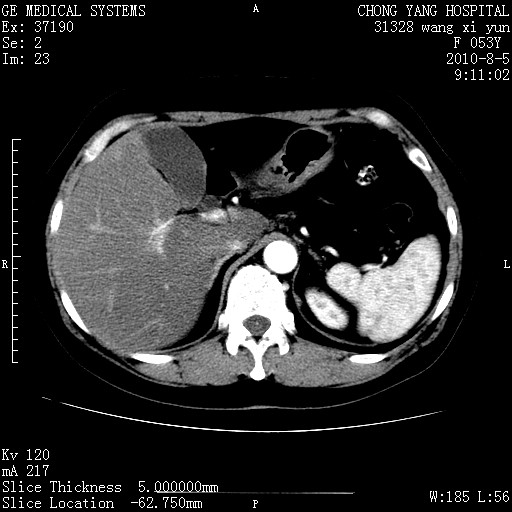

胆管细胞ca?

1)考虑肝左叶胆管细胞癌。2)脂肪肝。

支持胆管细胞ca。